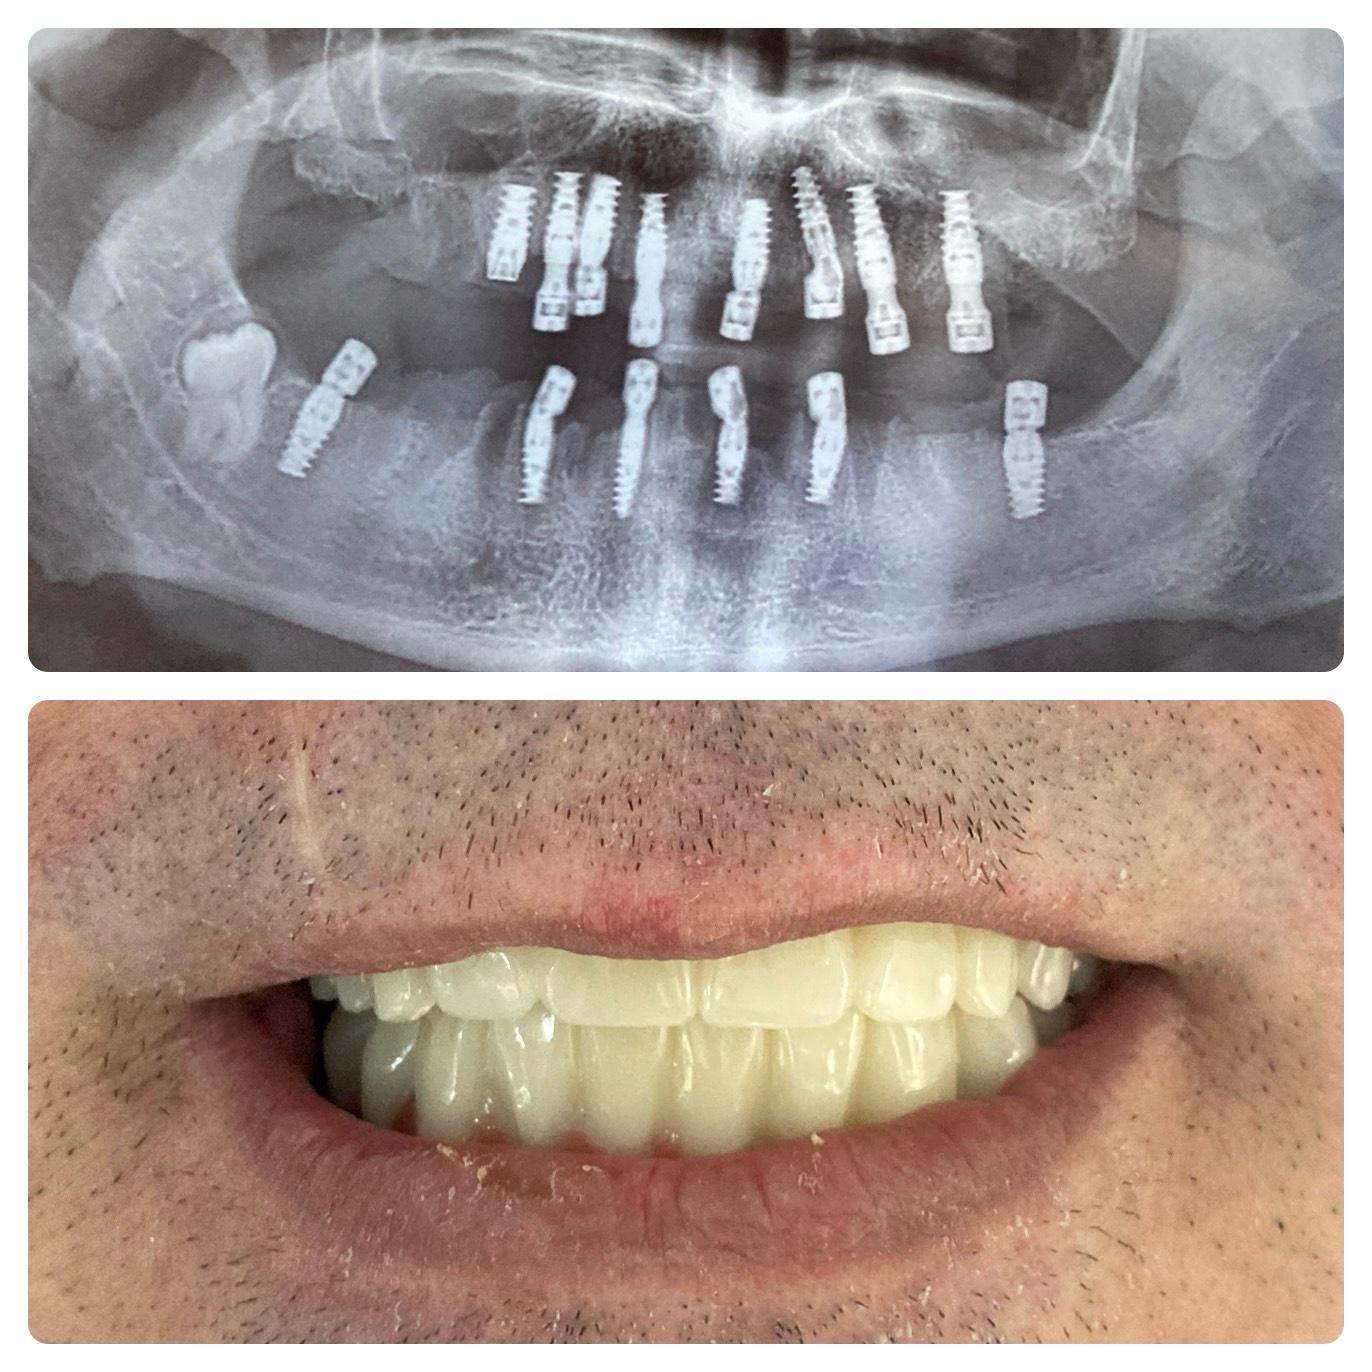

Si inizia con una consulenza e immagini 3D. Gli impianti vengono posizionati con precisione e restaurati con corone che appaiono e funzionano come denti naturali. L’intero processo è attentamente pianificato in fasi: valutazione, posizionamento dell’impianto, periodo di guarigione e restauro finale. Con le tecniche moderne, molte procedure sono minimamente invasive e spesso vengono fornite soluzioni temporanee, così da non rimanere mai senza sorriso durante il trattamento.

La maggior parte degli adulti sani può ricevere impianti. Una consulenza e un esame confermeranno se l’implantologia è adatta a ciascun paziente. Fattori come densità ossea sufficiente, gengive sane e condizioni mediche generali influenzano l’idoneità. Anche i pazienti con perdita ossea possono spesso ricevere impianti grazie a innesti ossei e tecniche chirurgiche avanzate, rendendo gli impianti possibili per una vasta gamma di casi.